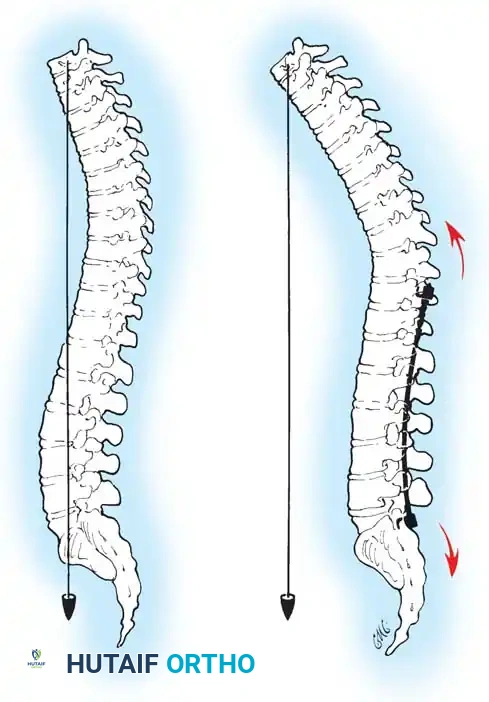

Biomechanics of Bone Grafting

Bone graft incorporates most effectively under compressive loads and is biologically disadvantaged in environments of distraction. Therefore, in scoliosis correction, if autogenous bone is limited, it should be preferentially concentrated on the concave side of the curve, which is subjected to compressive forces, rather than the convex side, which experiences tension. Furthermore, the farther the fusion mass is placed from the instantaneous axis of rotation, the more effectively it will neutralize movement across that axis.